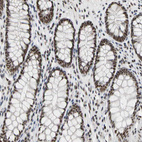

Immunohistochemical staining of human cerebral cortex, gastrointestinal, skeletal muscle and testis using Anti-FAM98B antibody HPA008502 (A) shows similar protein distribution across tissues to independent antibody HPA008320 (B).